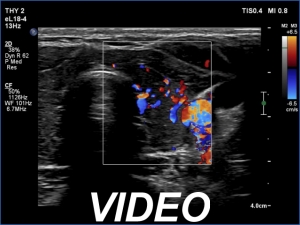

Ultrasonography. The thyroid was moderately hypoechoic and inhomogeneous. There was a deeply hypoechoic lesion in the isthmus which presented microcalcifications. Compared with the extranodular tissue, the nodule was much less vascularized on Doppler and microflow imaging but was harder on elastography.